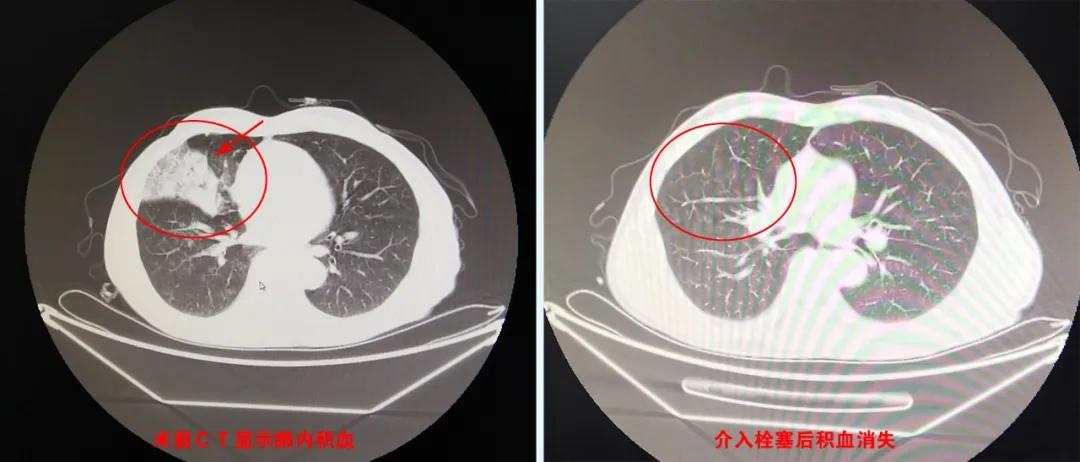

▲老李术前术后影像对比

当天傍晚到达荆门二医急诊科,急行CT提示“支气管扩张伴右肺积血、感染”。完善相关检查及核酸采样后,经血管介入科会诊确诊为“支气管扩张并发咯血”,随即转入流转病区给予止血、抗感染及对症治疗。

局部麻醉、于大腿根部右股动脉处穿刺、超滑导丝引导下至肺部支气管动脉——右肺支气管动脉明显增粗、迂曲、紊乱,注入造影剂,锁定渗漏部位。利用微导管技术迅速选入血管内,注入特殊栓塞剂“堵”住出血点,再次造影动脉出血随即消失。手术进行了约1个小时,术后老李咯血停止。

“介入栓塞治疗咯血成功的关键是通过术中的血管造影影像,找出‘肇事’血管、定位出血点,止血效果立竿见影。”荆门二医血管介入科主任李威表示,介入治疗是继内科、外科之后的第三大治疗学科,在内科药物疗效不理想、外科无法开刀的情况下,为众多急危重症和疑难病患,提供了崭新的诊断与治疗途径。